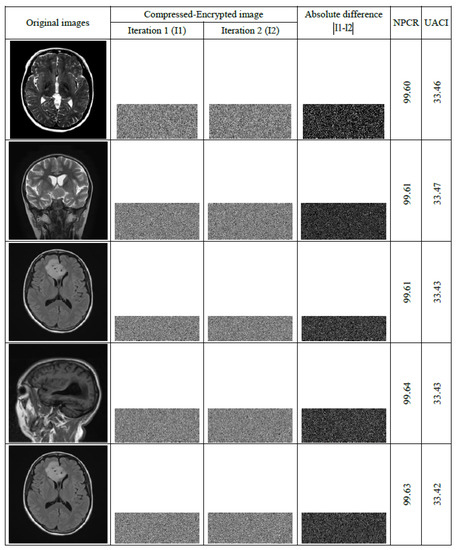

7.7. Differential Attack Analysis

Differential attacks can be used by IoMT attackers in their attempt to crack encryption schemes. To evaluate the effectiveness of our scheme in resisting such attacks, the Number of Pixels Change Rate ( N P C R ) and the Unified Average Modified Intensity ( U A C I ) are used as standard evaluation criteria. N P C R and U A C I are defined by Equations (28) and (29), respectively [61].

U A C I = i , j Im g i , j Img i , j 255 × H × W × 100 ; i = 1 , . . . , N and j = 1 , . . . , M

N P C R = 100 × i , j D i f i , j N × M with D i f i , j = 0 if Im g i , j = Img i , j 1 if Im g i , j Img i , j

where Im g i , j is the input medical image and Img i , j is the compressed–encrypted version of the input image.

The analysis test carried out in the previous subsection indicates that any minor variation of the key components causes non-recuperation of the input image. This benefit is exploited to resist brute-force attacks as follows:

• Set a constant of low value: Δ = 10 10 .

• Select a key parameter (e.g., λ 3 ) and add Δ to this parameter ( λ 3 * = λ 3 + Δ ).

• Use the proposed scheme for compression–encryption of the first medical image in the dataset by using the user-selected security key containing the modified parameter ( λ 3 * ).

• Update λ 3 * element by λ 3 * = λ 3 * + Δ .

• Apply compression–encryption to the second medical image in the dataset, and so on until the proposed scheme is applied to the entire dataset.

The above steps are designed to ensure that each image in the dataset is compressed–encrypted with a unique security key. That is, the same image file produces entirely different cipher-texts after being compressed–encrypted in two distinct iterations of our algorithm.

To evaluate the validity of the above procedure to withstand differential attacks, the test images shown in Figure 15 are compressed–encrypted in two consecutive iterations of our scheme. Then, N P C R and U A C I are computed for the output images. The comparison of N P C R and U A C I values produced through our scheme with those reported in [61], leads to the conclusion that the proposed scheme is indeed effective in resisting differential attacks.

Figure 15. Plain grayscale medical images of size 512 × 512 and their corresponding compressed–encrypted forms and the values of N P C R and U A C I .